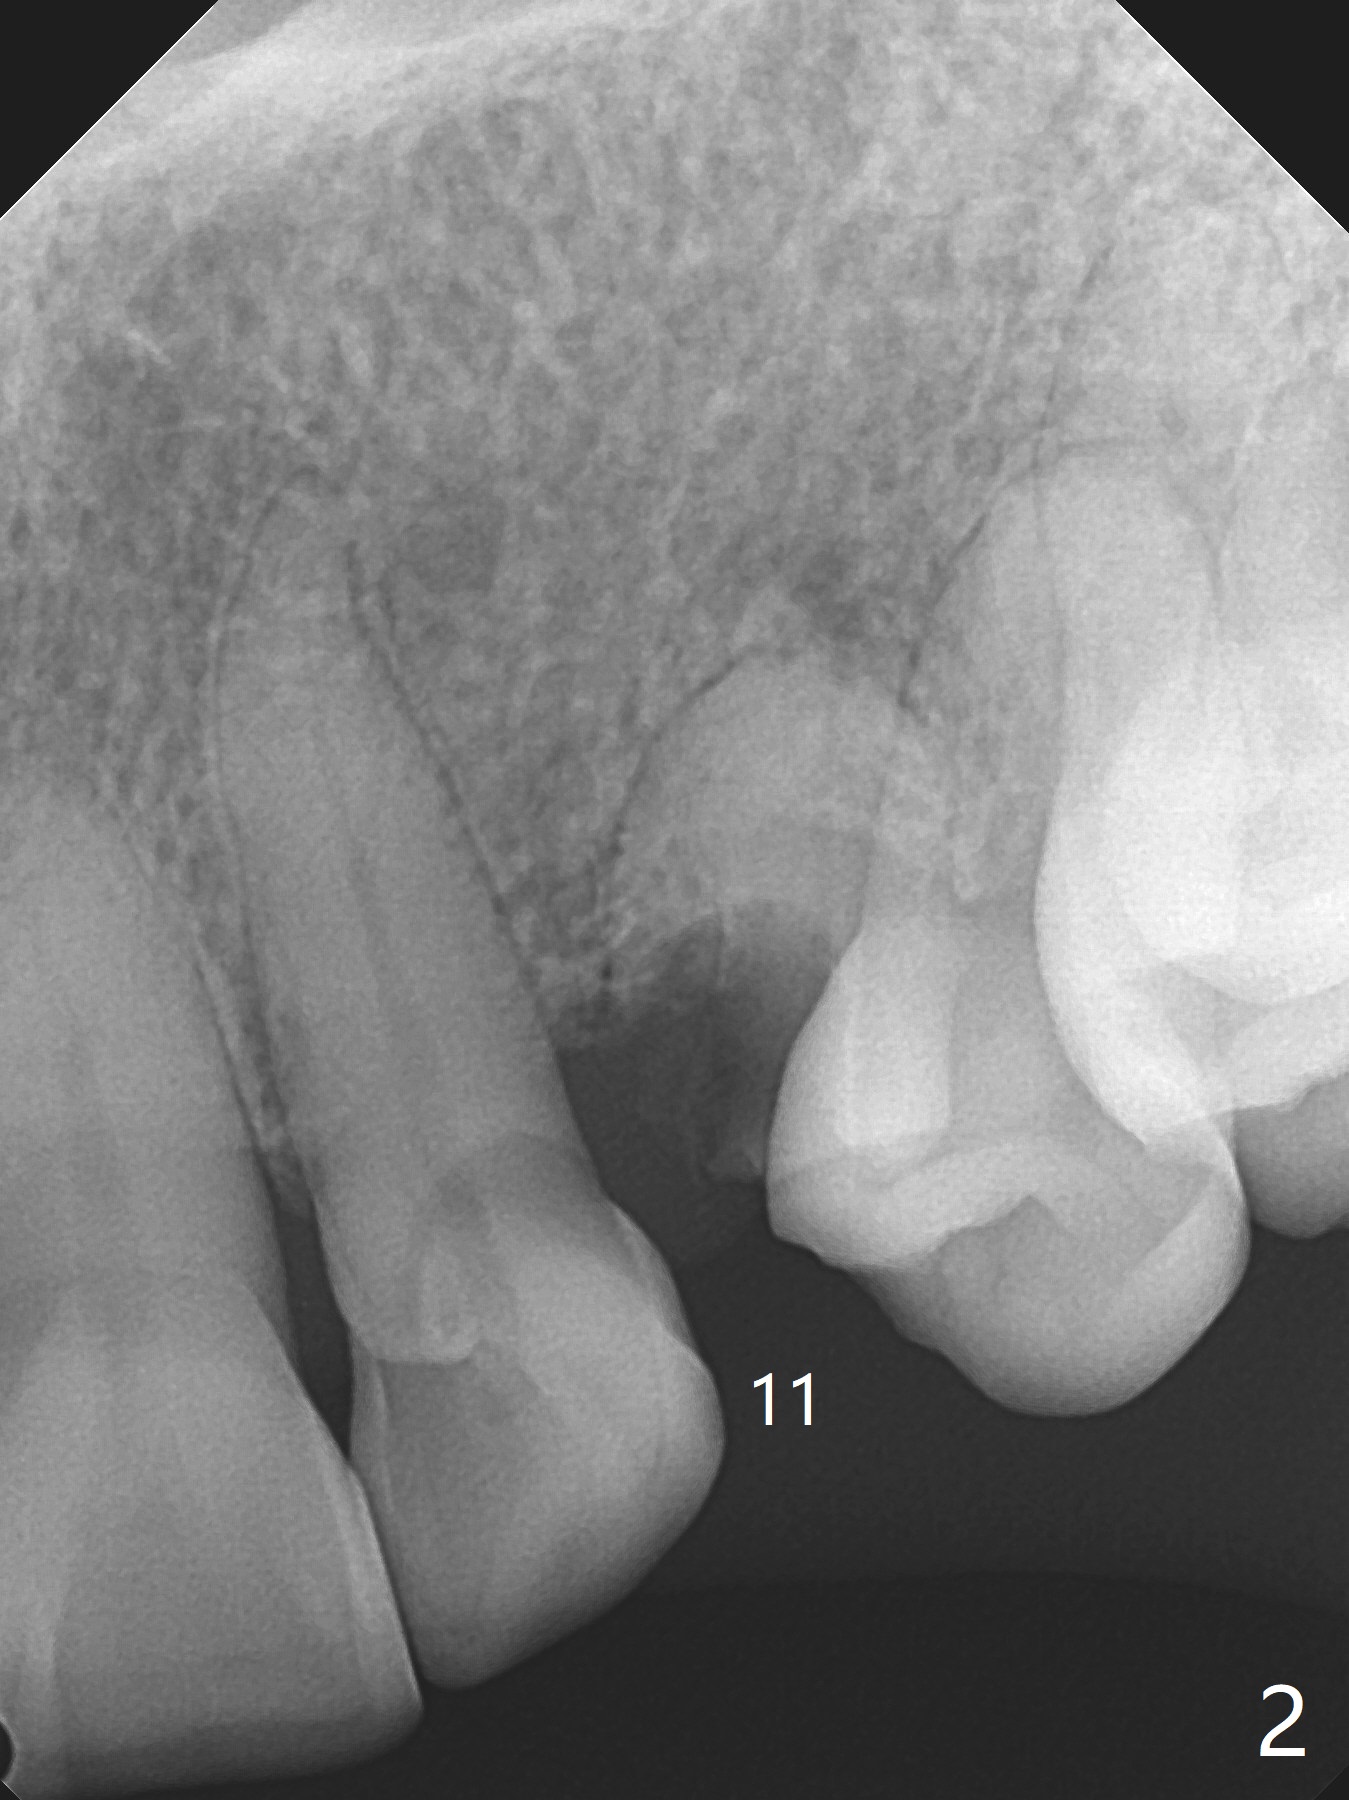

A 61-year-old woman with small statue, partial edentulism and bite collapse (deep bite) (Fig.1) requests an implant at #11 first (Fig.2). A 4x17 mm tissue-level implant is planned.